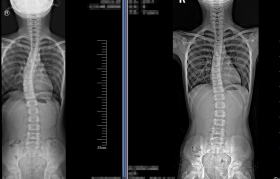

2. 度数迷思的破除 20度以下:通过瑜伽、游泳等对称性运动可完全矫正...

211